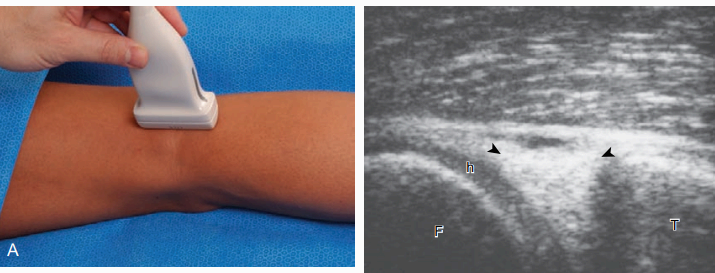

가쪽 구조물들을 검사하기 위해서는 종아리를 안쪽으로 돌리거나 환자를 반대편으로 약간 돌아 눕히면 된다. 가쪽에서 검사할 구조물에는 엉덩정강근막띠, 가쪽 곁인대, 넙다리 두 갈래 근힘줄 그리고 무릎의 뒤가 쪽 모퉁이에 있는 지지 구조물이 있다. 무릎힘줄의 아래 부위에서 긴 축영상으로 시작하며 이어서 탐촉자를 가쪽으로 움직인다. 무릎힘줄을 벗어나서 바로 다음에 보이는 가는 섬유다발 구조물이 엉덩정강근막띠인데 몸 쪽 정강뼈의(Gerdy tubercle)에 붙어있다. 보다 몸 쪽에서 엉덩정강근막띠와 넙다리뼈 사이를 검사하는 것이 중요한데 이는 엉덩정강근막띠 마찰증후군(friction syndrome)과 연관된 병변을 검사하기 위해 서이다. 관상면으로 놓인 탐촉자를 가쪽으로 움직여서 가쪽 넙다리뼈관절융기에 위치시킨다. 여기에는 오금근힘줄이 지나는 고랑이 있는데 중요한 뼈표식자(bony landmark)이다. 이 고랑이 확인되면 탐촉자의 몸 쪽 부분은 넙다리뼈에 고정하고, 먼쪽 부분을 종아리뼈머리 쪽으로 비스듬히 회전시킨다. 이 위치에서 높은 에코의 가쪽 곁인대가 보이며, 가쪽 넙다리뼈관절융기에서 종아리뼈머리의 가쪽 표면까지 뻗쳐있다. 가쪽 곁인대의 몸 쪽 부위는 넙다리뼈고린내에서 오금근힘줄 위로 지나간다. 환자의 무릎을 외반(valgus angulation) 상태에서 검사하면 가쪽 곁인대가 주름져 보일 수 있으며, 비등방성을 일으킬 수 있음을 알아야 한다.

무릎 가쪽 검사 환자의 반대편 무릎 위에 검사하는 무릎을 올리면 무릎이 내반(varus)되어 가쪽 곁인대가 주름지는 것을 최소화할 수 있다. 탐촉자를 가쪽 곁인대를 따라 종아리뼈 부착 부위까지 움직인 후 탐촉자의 아래쪽을 종아리뼈머리에 고정하고 위쪽을 뒤로 회전하면 넙다리 두 갈래 근힘줄이 보인다. 이 힘줄은 가쪽 곁인대보다 덜 치밀한 가는 섬유다발에코결로 보이며 몸 쪽으로는 낮은 에코의 근육과 연결되므로 인대와 구별된다. 가쪽 곁인대와 넙다리 두 갈래 근힘줄이 함께 종아리뼈의 가쪽에 부착하므로 초음파영상에서 약간 두껍고 불균질 하게 보인다. 넙다리 두 갈래 근힘줄의 관상면에서 탐촉자를 뒤로 움직이면 상대적으로 낮은 에코의 온종아리신경이 보이며, 환자를 엎드리게 한 후 뒤쪽에서 검사하면 신경의 몸 쪽부위를 더 잘 볼 수 있다. 무릎 뒤가 쪽 검사에서는 가쪽 곁인대, 넙다리 두 갈래 근, 그리고 온종아리신경의 상대적인 위치 관계를 확인한다. 다시 관상면에서 가쪽넙다리뼈관절융기에 오금근고랑으로 돌아와서 관절 뒤로 돌아가는 오금근힘줄과 인접한 섬유연골 및 가쪽초승달의 뒷뿔을 검사한다. 오금근힘줄이 비등방성 때문에 에코가 떨어지는 것을 힘줄의 이상으로 오해하지 않아야 한다. 오금근의 힘살(belly)은 정강뼈와 정강혈관 사이에 있다. 마지막으로 관절선에서 오금근힘줄에서 종아리뼈붓(fibula styloid)으로 연결되는 높은 에코의 구조물이 오금종아리(popliteofibular) 인대이다. 뒤가 쪽 모퉁이의 다른 지지 구조물들 중 활꼴인대와 가쪽장딴지종자뼈-종아리(fabellofibular) 인대 같은 것들은 찾기 힘들다.